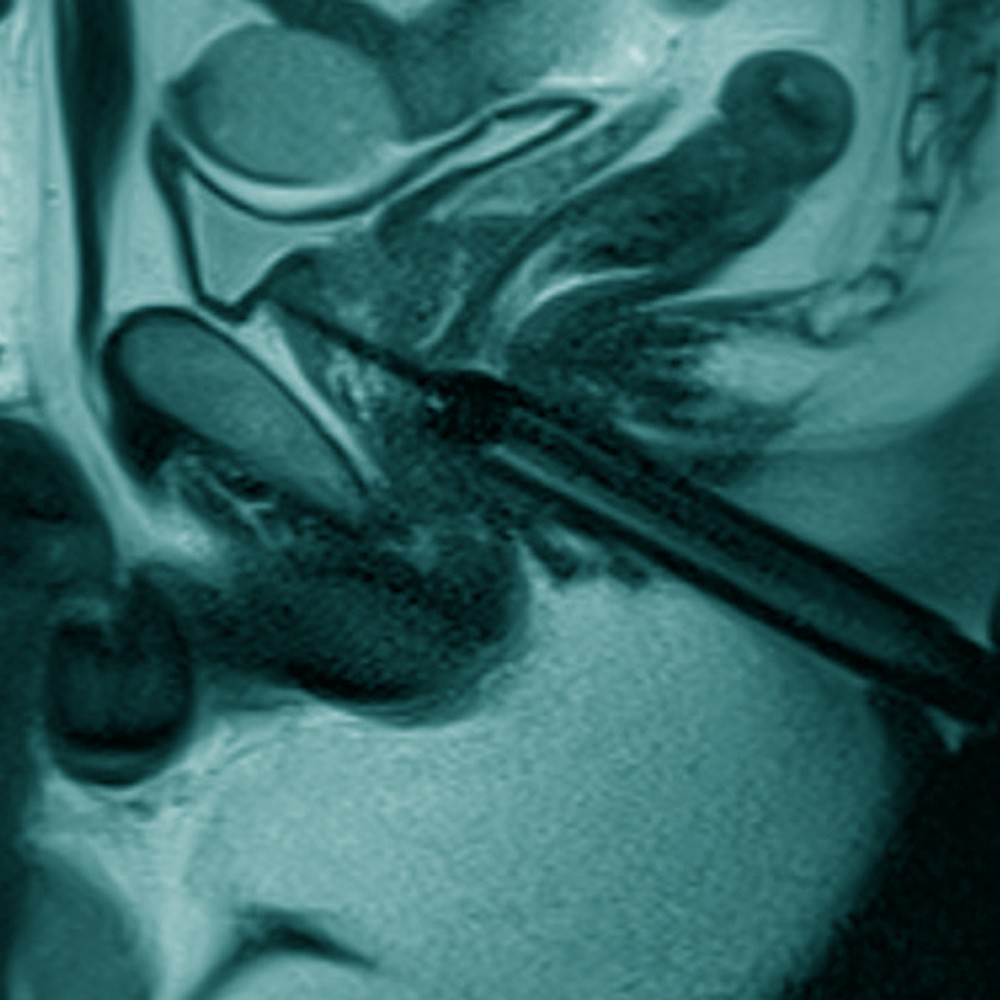

Willkommen zum 16. Petersberger Symposium – dem zentralen Treffpunkt für Expertinnen und Experten der klinischen Radiologie. Unter dem Motto „Radiologie meets Urologie“ widmen wir uns 2026 der Zukunft des Prostata-Screenings: von technischer Innovation über künstliche Intelligenz bis hin zu neuen diagnostischen und therapeutischen Standards.

• Fortschritte in der MRT-basierten Diagnostik

• Bildgeführte Biopsieverfahren